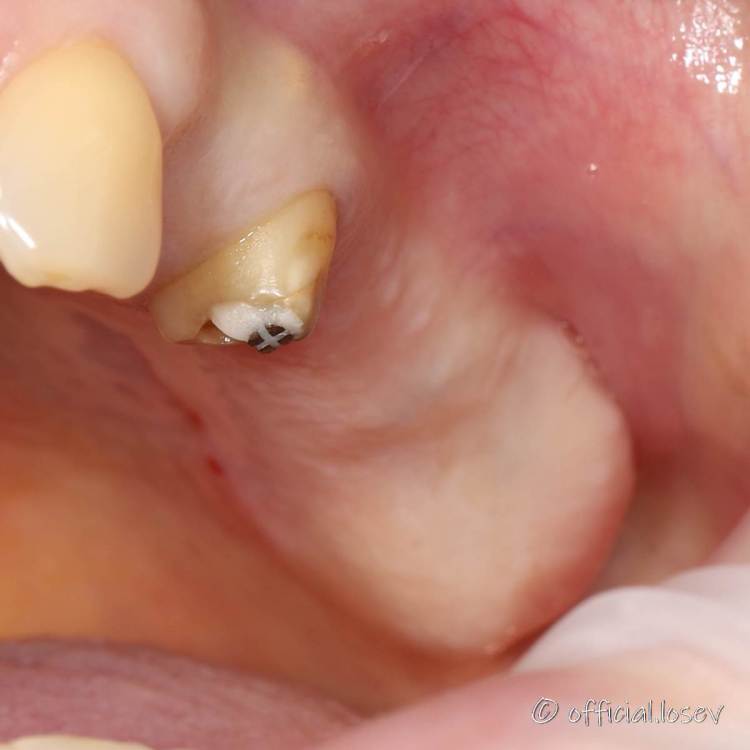

Ponchik Опубликовано 10 октября, 2021 Автор Поделиться Опубликовано 10 октября, 2021 (изменено) Шаблон отпилил ) И вот такое получилось в итоге. В области 1.5 остеотомом только в конце работал. В области 1.7 пилотом на 4.5-5мм по шаблону - далее остеотомами только. 4.8-6 встал с большим торком, но ставить формирователь я не стал (хотя порывался) Изменено 10 октября, 2021 пользователем Ponchik 1 Ссылка на комментарий